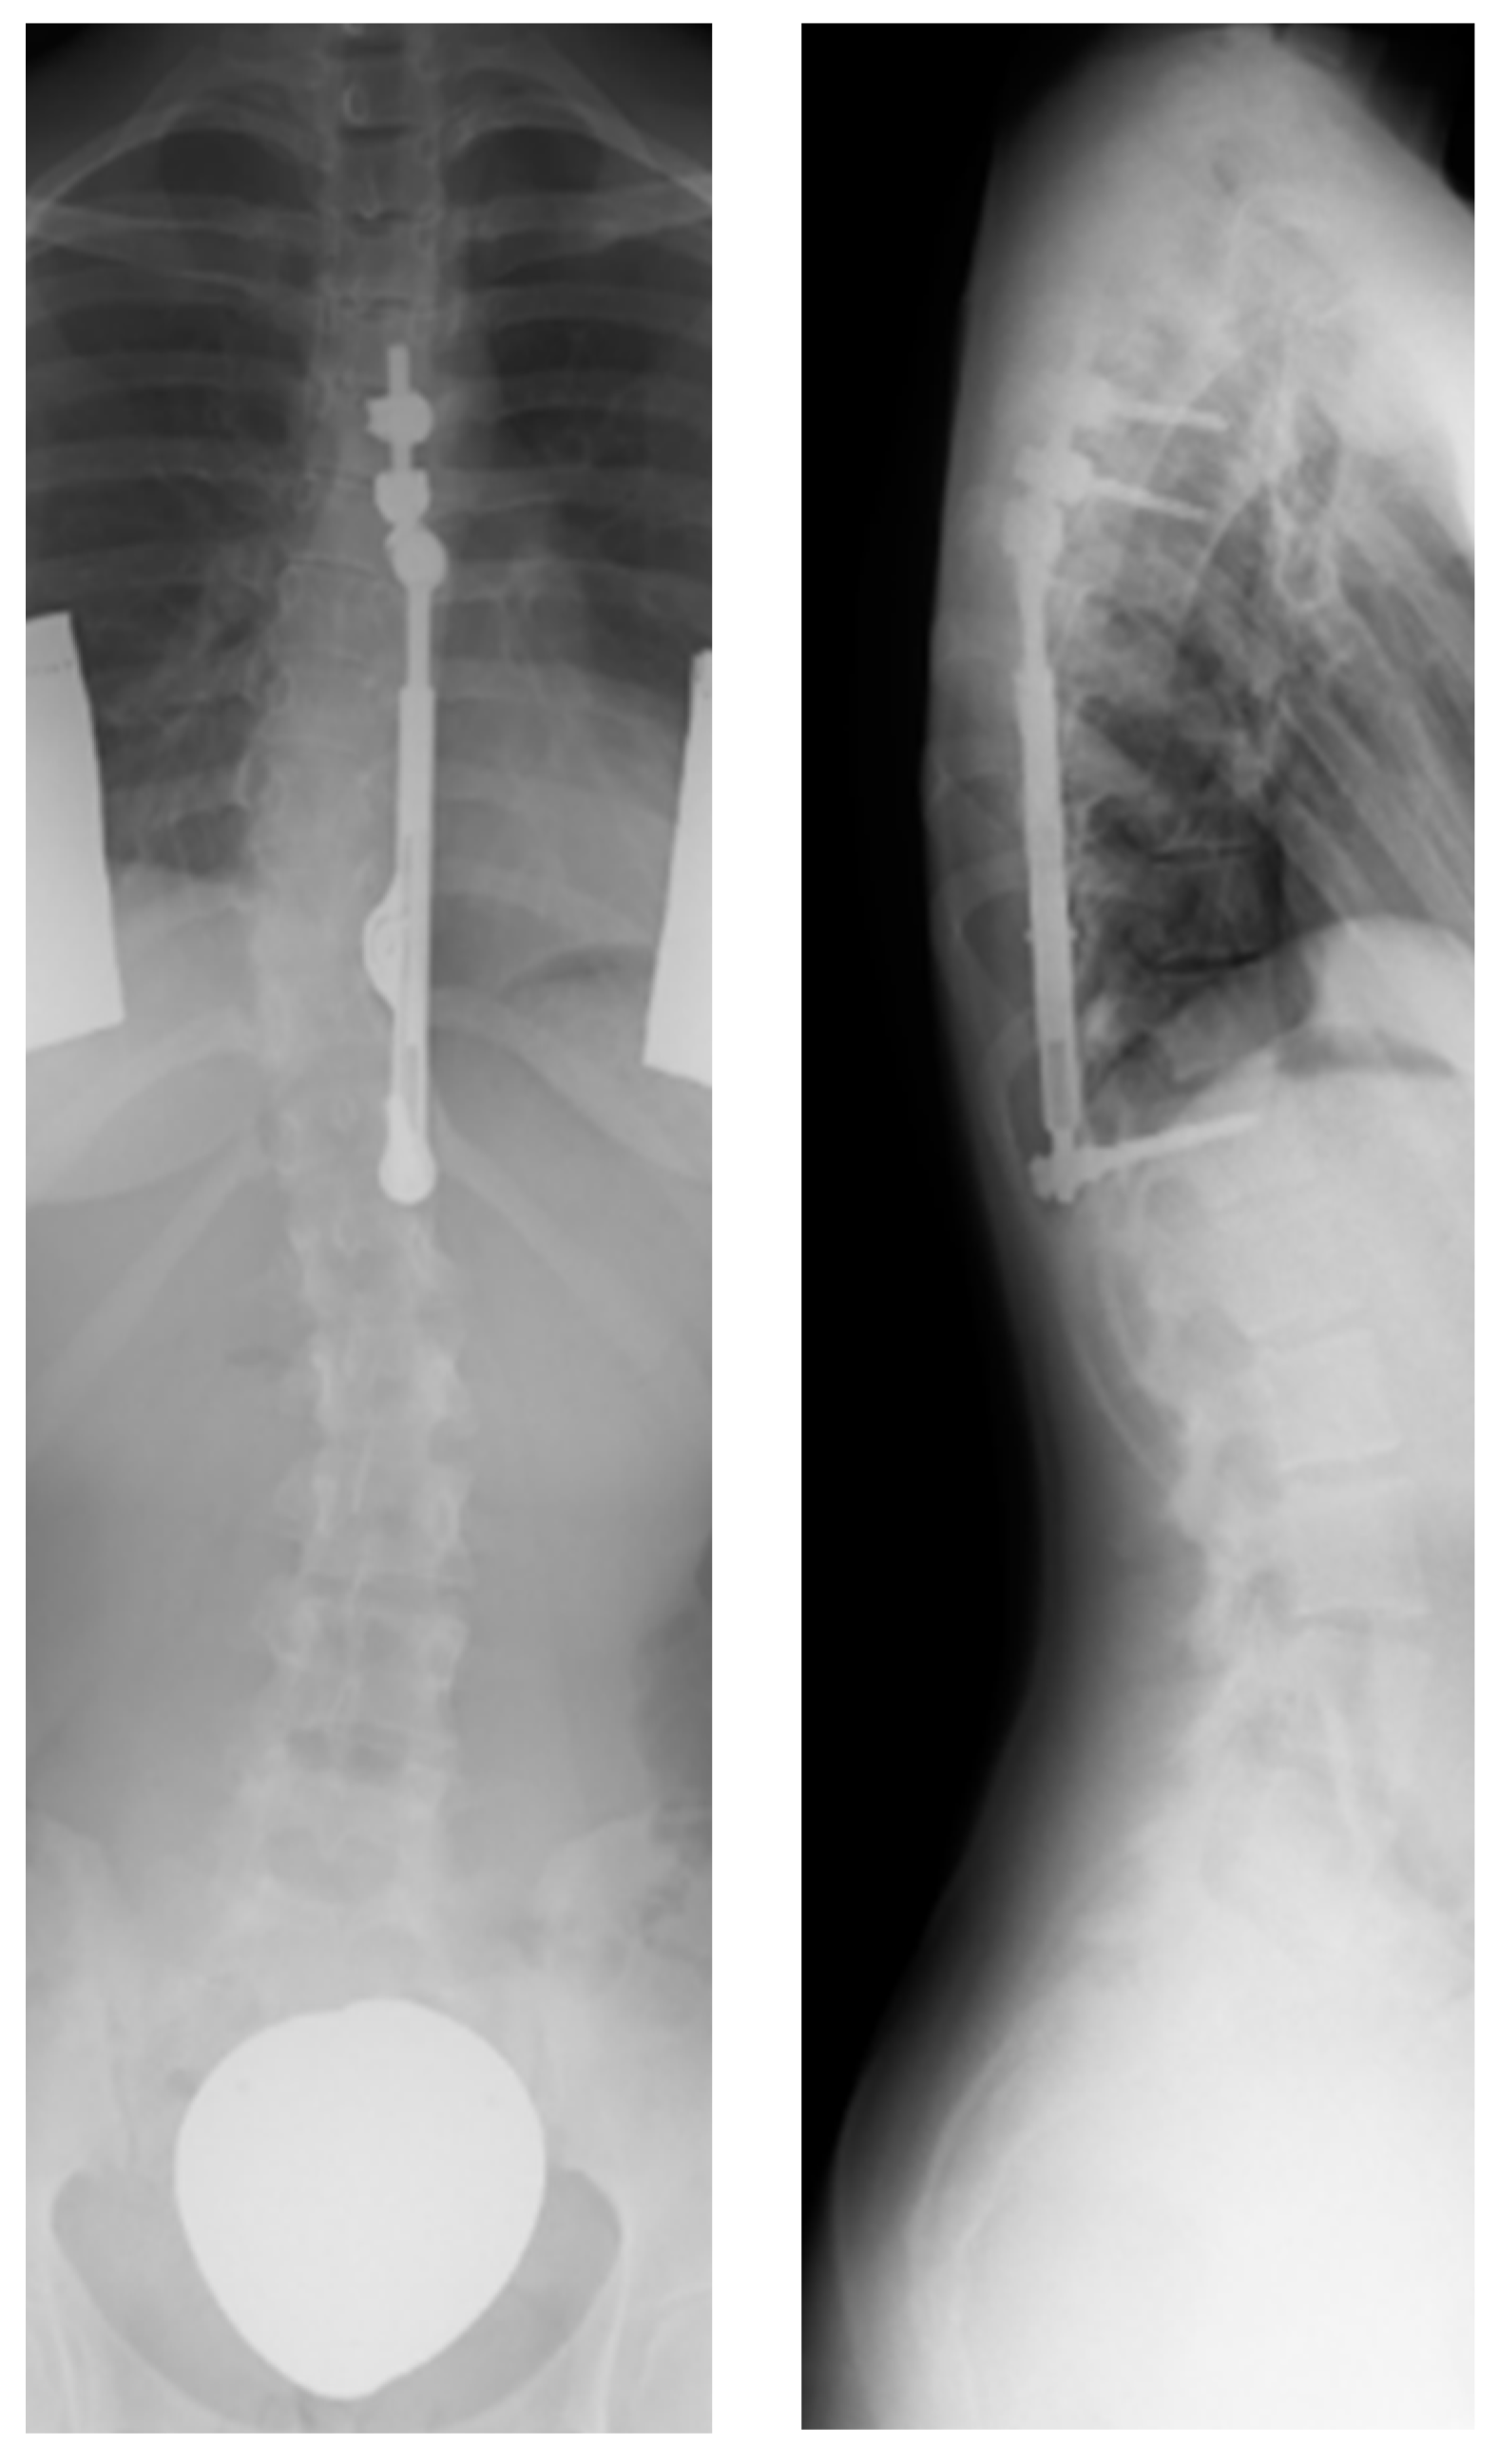

| 13 months | Maximum distraction distance reached after growth spurt, implant replacement with longer implant including renewed intraoperative distraction |

| 18 months | Maximum distraction distance reached after growth spurt, implant replacement with longer implant including renewed intraoperative distraction |

| 20 months | Maximum distraction distance reached after growth spurt, implant replacement with longer implant including renewed intraoperative distraction |

| 22 months | Maximum distraction distance reached after growth spurt, implant replacement with longer implant including renewed intraoperative distraction |